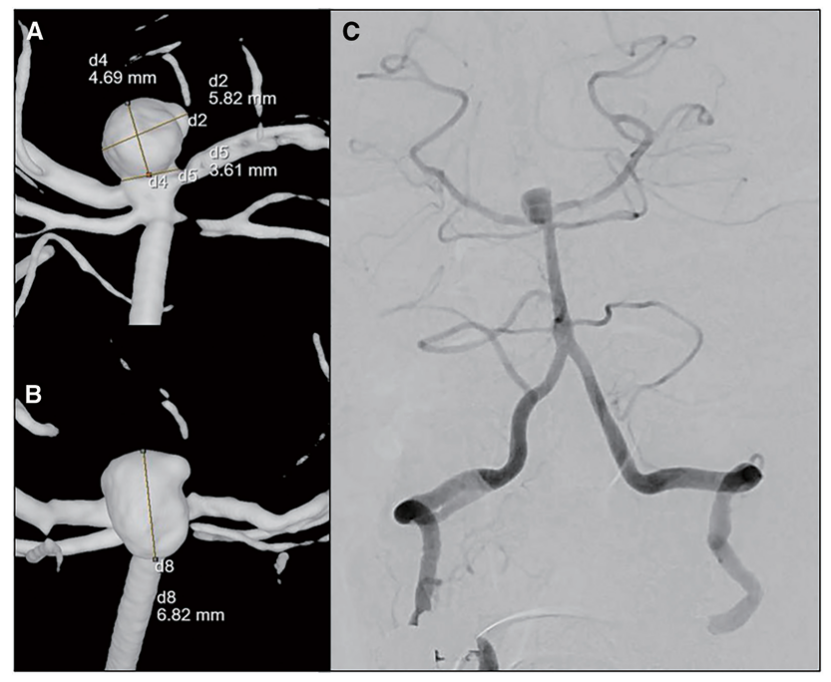

一名60岁的女性患者在我们医院就诊,主诉头晕。患者有高血压病史,每日服用5毫克氨氯地平。家族病史无异常。磁共振血管造影显示在基底动脉尖处约7毫米直径的未破裂脑动脉瘤(图1)。在与患者及其家人商议后,我们决定进行弹簧圈栓塞术以预防破裂。

图1:动脉瘤血管造影结果。(A,B,C)基底动脉顶端可见动脉瘤。